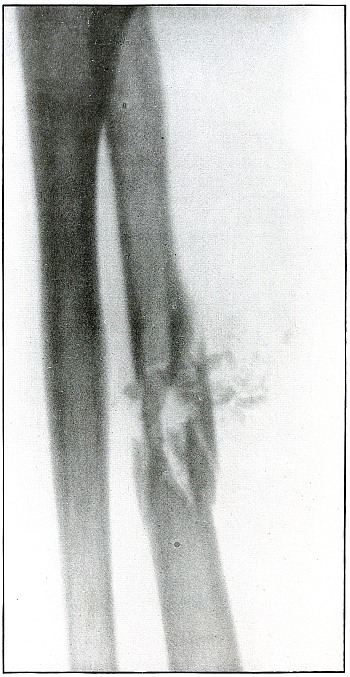

[Pg 88]

Plate 39.

[Pg 89]

Rifle—Plate 39.

UPPER EXTREMITY.

Gunshot Fracture of the Left Ulna.

The course of the bullet, with the velocity of long range, was

anteroposterior through the lower third of the forearm, striking the

outer side of the bone. The initial velocity of the projectile was

much reduced, as is shown by the tendency to puncture the bone without

much fragmentation.

There was no displacement of fragments as a direct result of the

impact, although muscular contraction has caused some slight

subsequent overriding.

The wounds of entrance and exit were about the same, if not quite

similar in appearance.

The emergency treatment is the conventional antiseptic dressing with

splint immobilization.

The subsequent treatment is usually that of a simple fracture,

as infection in such cases is rare.

[Pg 90]

Plate 40.

[Pg 91]

Rifle—Plate 40.

UPPER EXTREMITY.

Gunshot Fracture of the Ulna.

The course of the bullet was obliquely anteroposterior through the

lower third of the forearm, striking the radial edge of the bone with

a velocity of long range.

The wounds shown in plates 35 and 39

represent conditions similar to those causing this wound,

except that the ranges were progressively greater.

In this case the projectile exhibited a punching effect at the

point of impact, and although the lines of force are shown in

characteristically divergent fissures, the energy imparted to the

fragments—less than in the preceding cases—has not been sufficient

to separate or to displace the fragments.

The emergency and subsequent treatment is conventionally conservative,

as in the preceding cases.

[Pg 92]

Plate 41.

[Pg 93]

Rifle—Plate 41.

UPPER EXTREMITY.

Gunshot Fracture of the Wrist.

Wound of entrance, posterior aspect of forearm over the lower end of

the radius, with the bullet ranging forward and slightly downward to

the wound of exit and covering with great laceration the anterior

aspect of the wrist joint.

The range was close, and the energy of the high velocity of the

missile was imparted to fragments, which, becoming “secondary

missiles,” emerged with the projectile to cause extensive laceration

and destruction of tissue.

The case was received for amputation in the second week, when a grave

degree of infection extended in a cellulitis to the elbow. The ulnar

nerve and vessels were intact, but the flexor tendons were almost

entirely destroyed.

The plate, made after several weeks, when infection was under control

and after the end of the radius and fragments of the carpus had been

informally removed, shows a rarefaction of the carpus and proximal

ends of the metacarpus, due to infection and disuse.

Frequent incisions and extension of drainage, with removal of detached

fragments, was continued for several months. The wound was closed in

the sixth month, with ankylosis and deformity of the wrist,

as shown in plate 42.

[Pg 94]

Plate 42.

[Pg 95]

Rifle—Plate 42.

UPPER EXTREMITY.

Gunshot Fracture of the Wrist.

This plate, presenting a lateral view of the wound shown in

plate 41, shows considerable deformity of the

joint, after four months’ treatment, which was even more marked two

months later, when the case was discharged with an ankylosis of the

wrist joint, contracture of the flexor tendons of the fingers, and

slight flexor function of the thumb, permitting apposition with the

first finger.

The result, while leaving much to be desired, preserved a function of

the hand vastly superior to that of a forearm stump.

The treatment in such cases is always courageously conservative, with

amputation only as the extreme measure to save life, with risks of

judgment in favor of conservatism.

Corrective measures may be employed after management if the treatment

of the infection is successful and when the case passes out of the

military category. It is not possible, during a long infection, to

maintain better position in such cases.

[Pg 96]